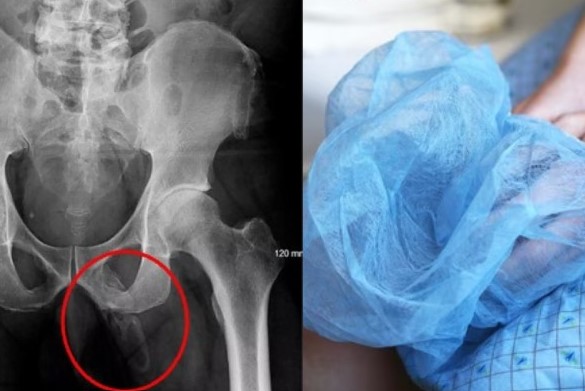

அமெரிக்காவின் நியூயார்க் நகரை சேர்ந்த 63 வயதான மனிதர் ஒருவர் முழங்கால் வலியால் சிகிச்சை பெற வந்த போது அதிர்ச்சியளிக்கும் விதமாக பெனிலின் ஓசிஃபிகேஷன்(penile ossification) என்ற அரிய வகை நோயால் பாதிக்கப்பட்டு இருப்பதை அறிந்தார்.

இதில், ஆணின் பிறப்புறுப்பில் கடினமான எலும்பு போன்ற அமைப்பு உருவாகும், இந்த அரிய நிலை இடுப்பு எக்ஸ்ரே பரிசோதனையின் போது கண்டறியப்பட்டது.

மருத்துவ தரவுகளின் படி, பெனிலின் ஓசிஃபிகேஷன் என்பது அரிதான நிகழ்வு, 40க்கும் குறைவான வழக்குகள் இதுவரை அறிக்கை செய்யப்பட்டுள்ளன.